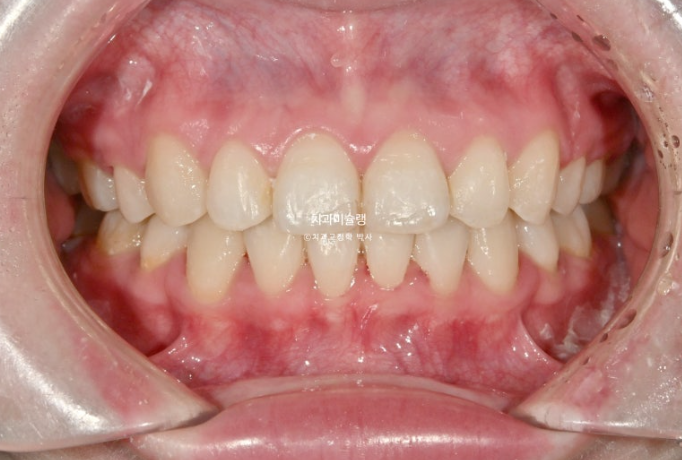

이제 전후 비교 보겠습니다.

파란 화살표 큰어금니가 입천장쪽으로 들어오면서 가위교합이 해소가 되었습니다.

예쁜 배열위에 고정식 철사 유지장치까지 붙은 모습입니다.

어긋나 있던 중심선은 정확히 맞으며 깊게 물리는 과개교합이 해소되어 이제 아래 앞니가 정상적으로 보입니다.

뿐만 아니라 치아 높낮이 불규칙으로 인해 들쑥날쑥 했던 아래 앞니가 배열되면서 잇몸라인도 어느정도 정리가 되었습니다.

파란 화살표 부분의 가위교합이 개선이 되면서 어금니 교합은 물샐틈 없는1급 교합관계를 보입니다.

심하게 뻗쳐있던 앞니가 정상각도를 찾았습니다.

이제 비로소 입이 편하게 다물립니다.

입매는 과하지 않게 적정량 예쁘게 들어갔습니다.

돌출입이 해소가 되면 비순삭이 줄면서 코도 높아보입니다.

앞니가 뒤로 6mm 이상 들어갔고 통상 발치교정보다 더 많은 양이 들어갔지만, 교정 후 옥니 등 부작용은 보이지 않습니다.

치아의 변화만큼 입매 변화도 드라마틱 합니다.